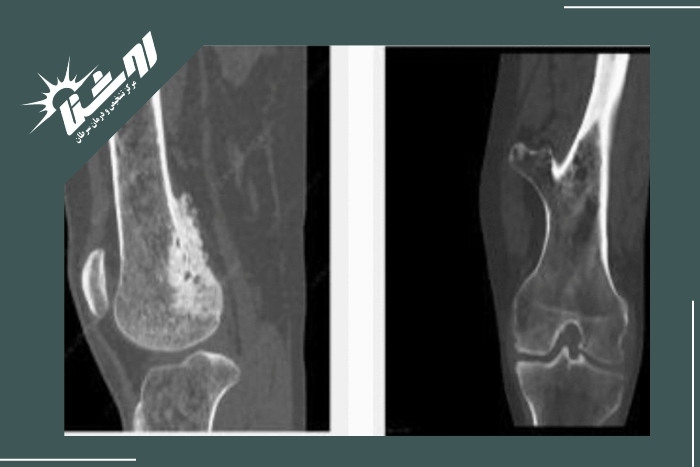

MRI برای مشاهده دقیق مغز استخوان، بافت نرم، تومورها و عفونت‌ها.

CT Scan جهت ارزیابی ساختار استخوان و شکستگی‌های پنهان.

اگر در تصویربرداری ضایعه‌ای مشکوک دیده شود نمونه‌برداری از استخوان انجام می‌شود که دقیق‌ترین روش برای تشخیص سرطان استخوان است.